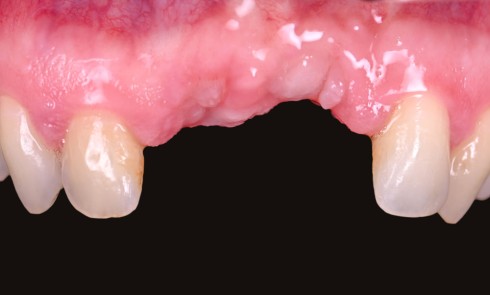

Quelles sont les spécificités de la pressée sur zircone ? Quelle est sa mise en oeuvre ? Comment analyser les échecs pour une fiabilité à longue échéance ?